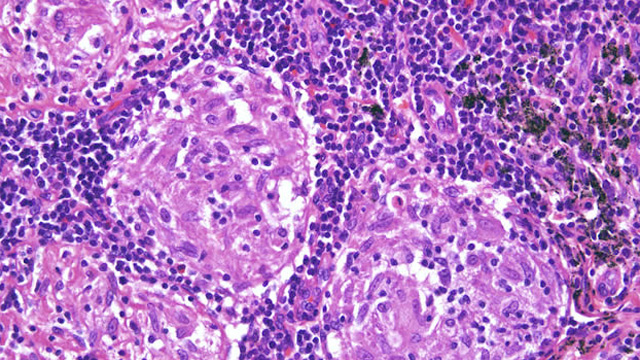

GANGLIO CENTINELA Procedimiento especializado para cáncer ginecológico, mediante el cual se realiza la extracción del primer ganglio del drenaje linfático, evaluando si hay compromiso o no por enfermedad. |